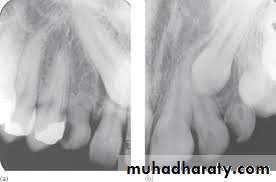

The radiographic views that can be used include;periapical, occlusal, OPG, lateral skull view cone beam CT (CBCT) can also be used. The

periapical radiograph provides a detailed view of the tooth, surrounding bone, root formation, the presence of root resorption of the adjacent lateral incisor or the presence of any pathology. Localization of the canine is important especially when it can not be determined clinically. Methods of localization include:

• Buccal object rule (parallax method, tube shift technique) in which two periapical films are taken, shifting the tube horizontally distally between exposures, if the un-erupted tooth moves in the same direction in which the tube is shifted it is localized palatally, if it moves in opposite direction it is buccally located, in a rule called SLOB (Same Lingual Opposite Buccal).

• In shifting the tube vertically inferiorly between exposures; the buccally located tooth will move inferiorly while the palatally impacted tooth will move superiorly.

• Vertex occlusal projection; which produces an axial view of the incisors, will demonstrate the bucco-palatal localization of the canine.

• Periapical occlusal method; uses a standard periapical view and an occlusal view to give two different views of the impacted tooth.

• OPG; can be used to localize impacted canine on the basis that palatally impacted canine appear magnified. It can also demonstrate the vertical angulation and its height.